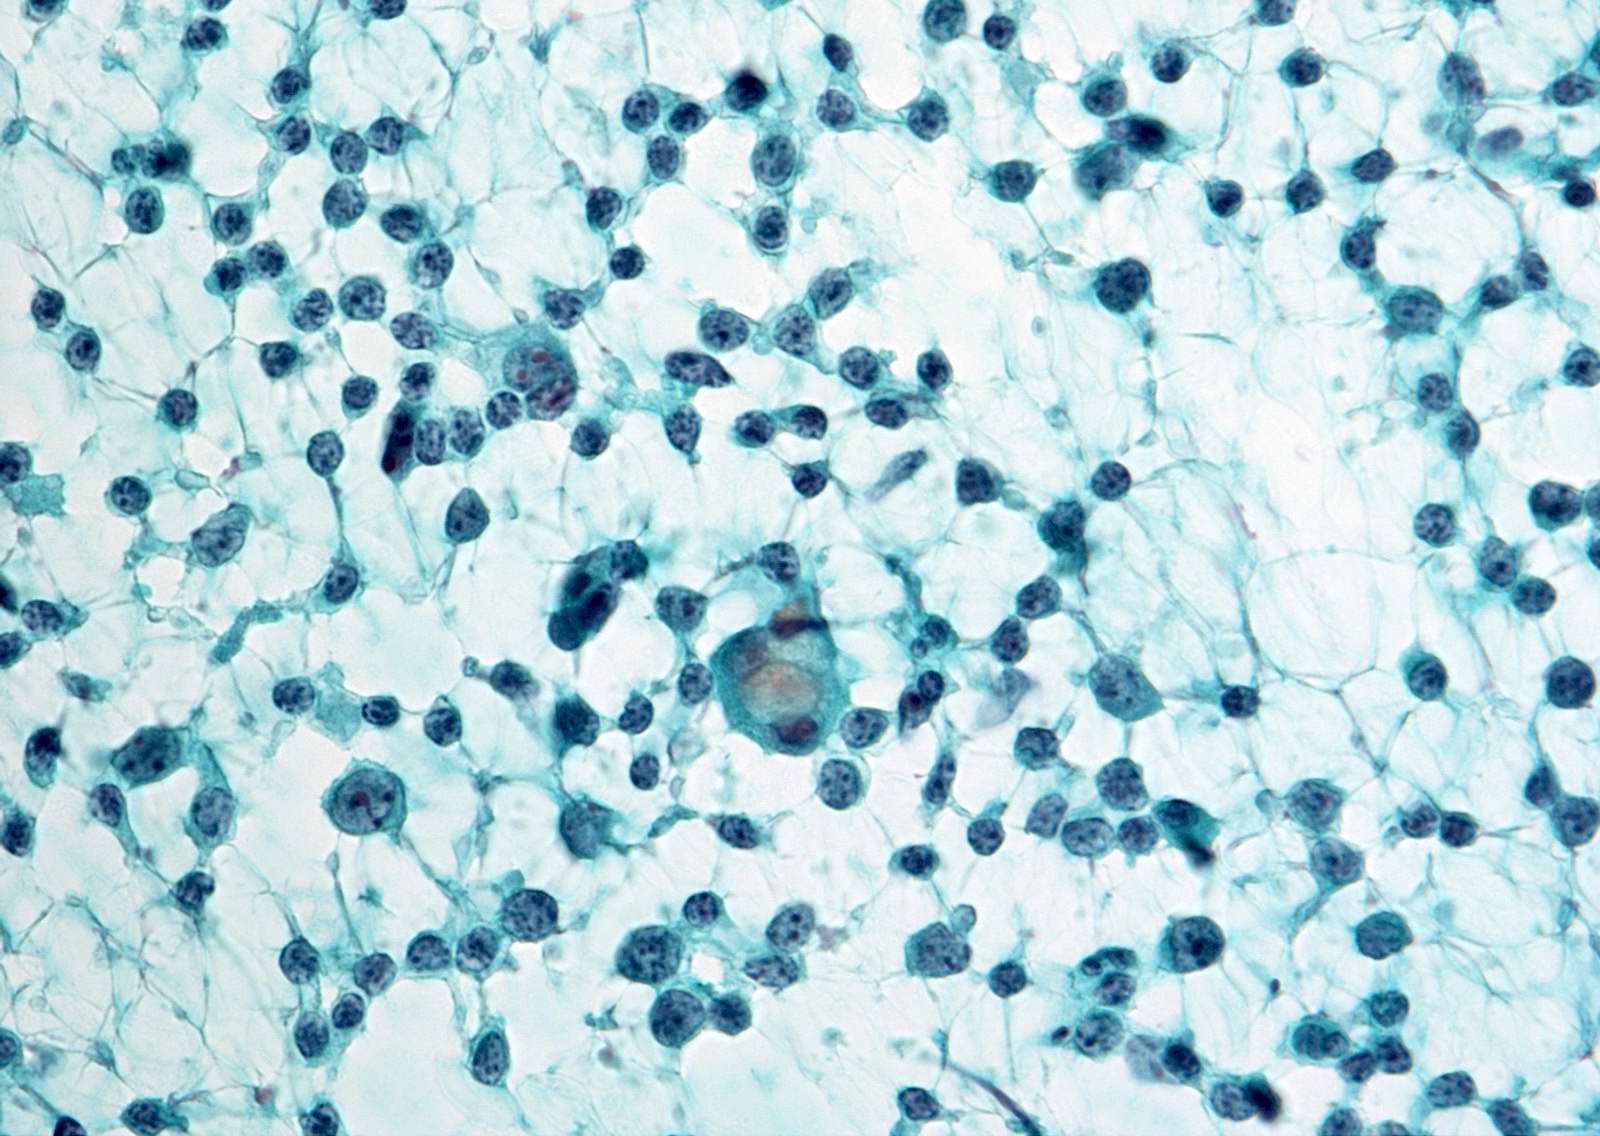

Cytology images

Contributed by Ayana Suzuki, Ph.D.

- Atypical lymphoid cells, rule out lymphoma:

- There is an atypical lymphoid infiltrate but the degree of atypia is insufficient for suspicious for malignancy

- Repeat aspirate for flow cytometry is desirable

- Parathyroid lesion:

- Triangular cell clusters with 1 sharp corner (wedge pattern), salt and pepper chromatin and no colloid (Head Neck 2002;24:157, Acta Cytol 2004;48:133, Diagn Cytopathol 2021;49:70)

- 25 - 30% of parathyroid lesions can be recognized

- Immunohistochemistry (especially GATA3 antibody) and ancillary studies (parathyroid hormone assays, molecular studies) can confirm the diagnosis (Diagn Cytopathol 2021;49:70, Endocr J 2016;63:621)